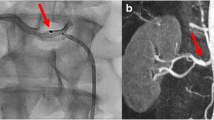

This study systematically evaluated consecutive patients who underwent donor nephrectomy and preoperative 64-channel multi-detector computed tomography (MDCT) angiography, which is more sensitive and accurate than conventional angiography. We aimed to estimate the frequency of small renal arteries10,16, investigate the anatomical background and suboptimal efficacy of catheter-based denervation through a quantitative analysis of the accessory renal artery and early-branching artery that cannot be performed using the previous catheter-based intraluminal intervention, and develop a new therapeutic strategy (Fig. 1).

Multi-detector computed tomography angiography of the renal artery. (a) Main renal arteries and an early branching renal artery. (b) Main renal arteries and an accessory renal artery. The same numbers in (a1, b1) indicate the same arteries in (a2, b2). (c) A branching accessory renal artery (red arrowhead), main arteries, an early branching artery. The main, accessory, and early branching arteries are yellow, red, and blue arrows, respectively.

Basic characteristics of the 314 donors were examined. The number, diameter, and length of the main renal artery (≥ 3 mm in diameter), accessory renal artery, and early-branching artery were evaluated. The largest artery from the aorta was defined as the main renal artery (Fig. 1a). The accessory artery was defined as the subartery branching directly from the aorta (Fig. 1b). The early-branching artery was defined as the early branching subartery (within 2.5 cm of the aorta) from the main renal artery (Fig. 1a,c)27,28. In addition, an early branching artery from an accessory artery was defined as a branching accessory artery (Fig. 1c). The diameter was measured at 3-mm intervals from the originating portion of the aorta to the division point in two or more consecutive branches measuring ≥ 3 mm in diameter. The diameter of the artery was defined as the length of the cross-section perpendicular to the direction of the artery running at the measurement site (Fig. 2a). The length of the main renal artery was defined as the length from the originating portion of the aorta to the division point in two or more consecutive branches measuring ≥ 3 mm in diameter (Fig. 2a)16.